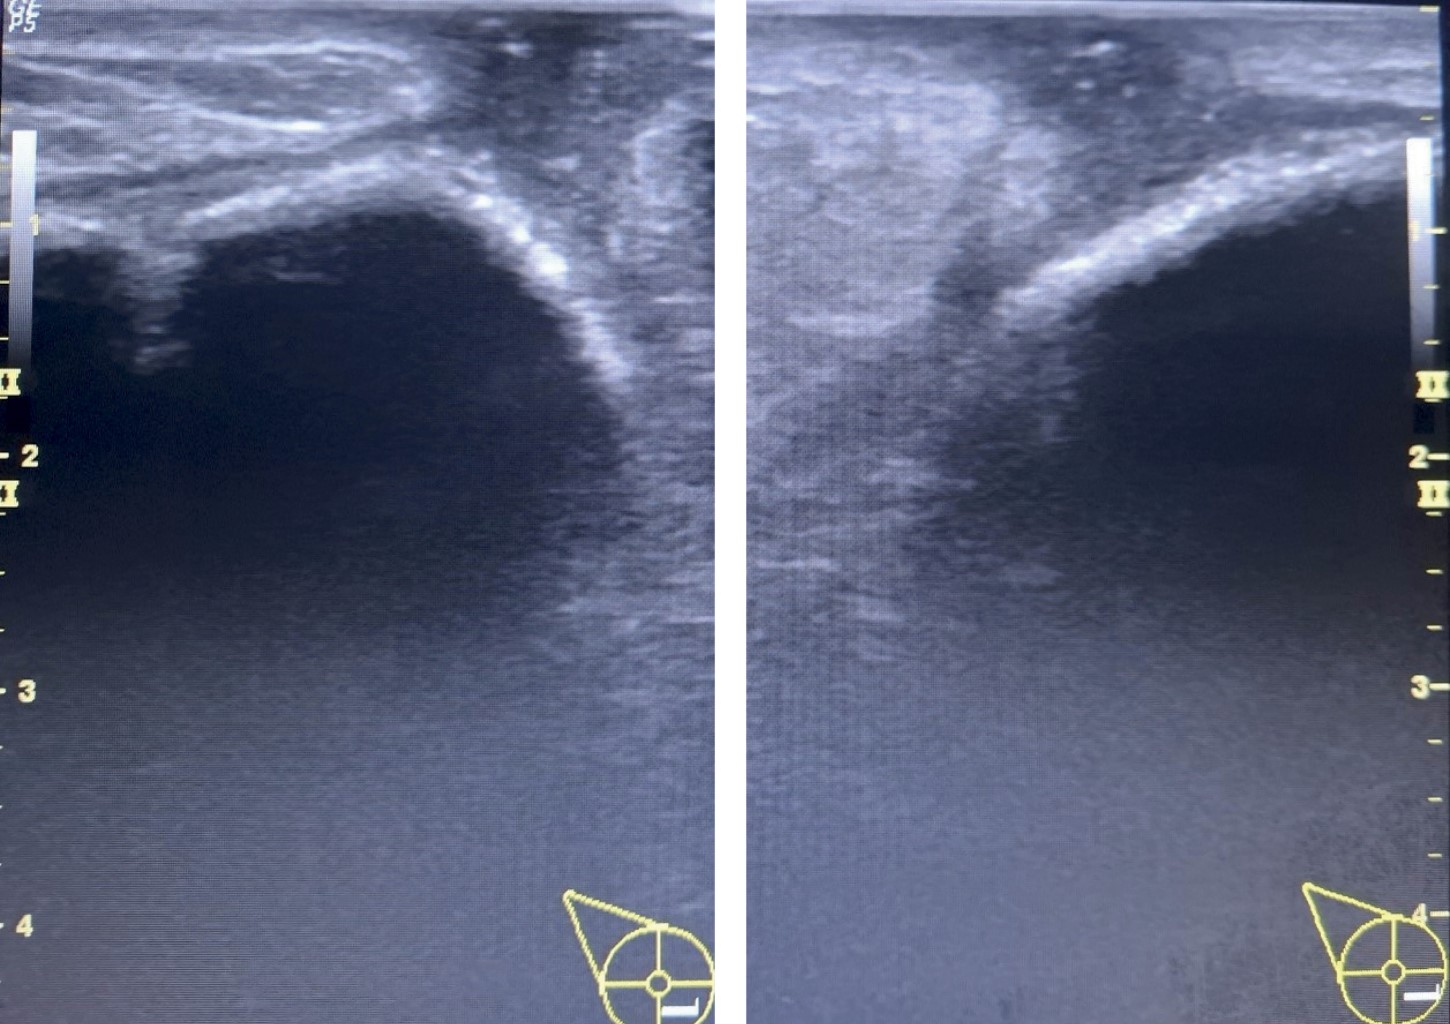

Fistula associated with breast implants in a patient with capsular contracture, a rare complication

Fistulas associated with breast implants are unusual complications of augmentation mammoplasty, occurring only in 0.1% of primary implant surgery, especially in reconstructive cases. Few bibliographic reports exist worldwide that which highlight their rarity. Breast imaging supports diagnosis and confirms surgical treatment. We present the case of a patient with aesthetic breast implants, who developed bilateral capsular contracture, and attended a specialized consultation 15 years after her initial surgery, with serosanguineous fluid discharge from her breasts. After confirming the fistulous tract from skin of the breast to the capsular space, we performed surgery, achieving satisfactory results.